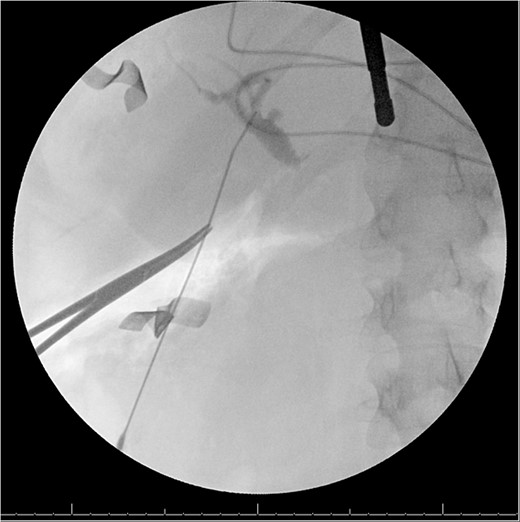

A 49-year-old female with a history of ADPKD and multiple liver cysts, 13-months status post subtotal cholecystectomy, endoscopic retrograde cholangiopancreatography with biliary sphincterotomy and balloon stone extraction, presented to the emergency department with fever and a 4-day history of discomfort in the right upper quadrant. At the time of the initial cholecystectomy, total cholecystectomy could not be performed due to extensive adhesions, and subtotal cholecystectomy with complete evacuation of the stones was done instead. Magnetic resonance cholangiopancreatography (MRCP) done at that time showed a dilated common bile duct (CBD) to 1.5 cm, intra and extrahepatic biliary dilatation, multiple liver cysts measuring up to 2 cm, and multiple stones in the CBD, including at the level of the ampulla (Fig. 1). Computerized tomography scan at the time of the second admission showed acute cholecystitis and she had mildly elevated transaminases, but there was no evidence of cholestasis or pancreatitis. MRCP showed minor proximal intrahepatic biliary dilation and cholelithiasis but no duct calculi (Figs 2–4). A laparoscopic cholecystectomy was attempted with extensive adhesiolysis between the gallbladder and surrounding omentum and mesocolon, but the cystic duct could not be isolated, and ultimately the cased was converted to open. While removing the gallbladder in a top-down fashion, a small bile leak was identified right at the closed end of the gallbladder remnant, where the bile duct was adhered to the gallbladder wall. Intraoperative cholangiogram was obtained through a small perforation in a right posterior bile duct at the site of attachment, which showed right posterior, right anterior and left hepatic ducts of equal size converged at a trifurcation (Fig. 5). The duct was repaired over a T-tube and observed throughout the rest of the case and no bile leak was identified. The gallbladder was opened along its lateral edge, revealing a hugely dilated cystic duct with ~10 to 12 marble-sized stones packed within the gallbladder remnant and cystic duct down to the juncture with the common bile duct. All the stones were removed and the safe portion of the gallbladder remnant was resected leaving the side attached to the bile duct in situ due to the Mirizzi anatomical variant. The cystic duct was oversewn along with the remnant of the gallbladder wall. Pathology showed acute-on-chronic cholecystitis with cholelithiasis. Repeat MRCP showed no retained stones in the biliary tree. The recovery course was unremarkable.

Intraoperative cholangiogram from second procedure demonstrating trifurcation of the right posterior, right anterior and left hepatic ducts, as well as a dilated cystic duct.